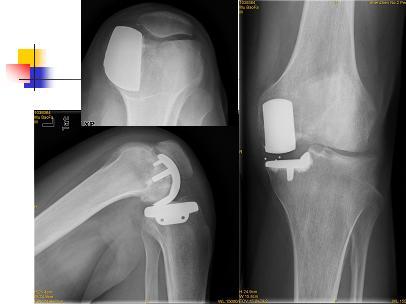

膝关节单髁置换

男性,25岁,行走疼痛2年。

术中见单髁破坏严重,病理为:剥脱性骨软骨炎

膝关节软骨损伤

骨炎